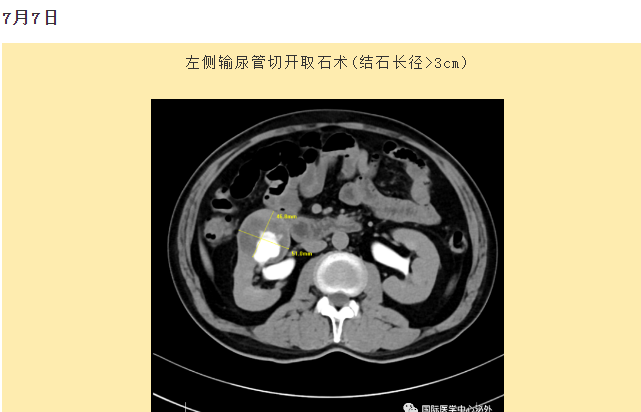

西安國(guó)際醫(yī)學(xué)中心醫(yī)院順利完成了達(dá)芬奇Xi(第四代)機(jī)器人裝機(jī)。7月6日—7月15日,泌尿外科成功完成了達(dá)芬奇Xi(第四代)機(jī)器人手術(shù)6例,標(biāo)志著科室微創(chuàng)外科邁入新時(shí)代,造福萬千患者。